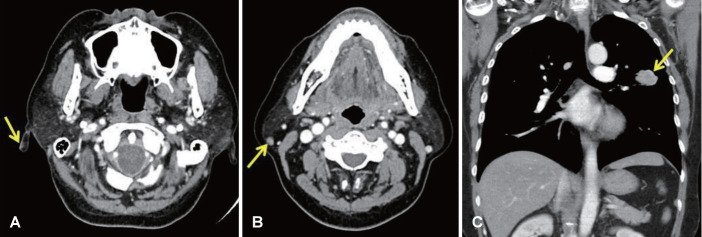

Merkel cell carcinoma (MCC) is an aggressive neuroendocrine carcinoma with a high rate of metastasis. MCC is rarely suspected during clinical examination, thus requiring biopsy to establish a pathologic diagnosis. In addition, MCC sometimes occurs in double primary cancers. Although there have been reviews on double primary cancers, only a few cases involving MCC have been described. Herein, we report a case of a 54-year-old female patient who presented to our clinic with a diagnosis of earlobe MCC following an excisional biopsy performed by another clinic. Further evaluation, including chest imaging, revealed a mass in the lung. The patient underwent a wide excision of the right earlobe, and video-assisted thoracic surgery on the lung. Pathology confirmed MCC in the right earlobe and adenocarcinoma in the lung. The patient underwent postoperative adjuvant chemotherapy followed by radiotherapy. Up to this point, 3 years after the surgery, there has been no evidence of recurrence.